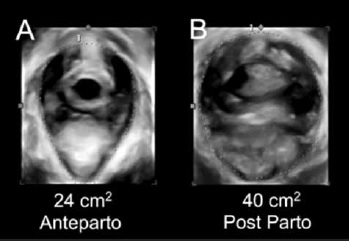

El trauma obstétrico del piso pélvico se encuentra relacionado directamente con el riesgo de desarrollar patologías del piso pélvico. Recientemente se ha vuelto claro que el trauma del piso pélvico compromete mucho más que el trauma perineal o “aquello que uno debe suturar en la sala de parto”. El músculo elevador del ano (MEA) se puede ver afectado con el paso del feto por el canal del parto. Se ha establecido una incidencia de un 10 al 30 % en la avulsión del músculo elevador del ano posterior a un parto vaginal(10,11). La avulsión o trauma macroscópico del MEA consiste en la desinserción completa o parcial del haz puborectal de la rama inferior del pubis, que puede ser evidenciado por medio del estudio de imágenes a través de la resonancia nuclear magnética o el ultrasonido de piso pélvico (Figura 1). La presencia de una avulsión del MEA determina la pérdida de la estructura integral del soporte del piso pélvico, gatillando secundariamente el descenso de los órganos pélvicos, especialmente del compartimiento anterior (cistocele) y apical (prolapso uterino o de cúpula vaginal)(12). La sobredistención del hiato urogenital o “microtrauma” es otro tipo de lesión que puede sufrir el MEA como consecuencia de un parto vaginal. Este tipo de trauma puede ser gatillado por el daño de la microestructura de las fibras musculares dada la sobredistención que se produce en el momento que el producto de la concepción atraviesa el canal del parto. Otra explicación de este fenómeno podría corresponder a la lesión de las estructuras vasculares y nerviosas por la compresión de la cabeza del feto en la segunda fase del trabajo de parto que terminarían afectando en forma directa a las fibras musculares del MEA. La sobredistención del hiato urogenital corresponde al cambio en el área del hiato urogenital al realizar maniobra de valsalva de al menos un 20% comparado con el estado previo al parto(13) (Figura 2). Estas alteraciones no siempre se asocian con la aparición de síntomas como la incontinencia urinaria o prolapso genital, pero constituyen un factor de riesgo establecido muy importante(14,15). Por otro lado, las lesiones del esfínter anal como consecuencia del parto vaginal se encuentran directamente asociadas con el desarrollo de incontinencia fecal(6). Estas corresponden al desgarro perineal de III grado, lesión que compromete el esfínter anal y al desgarro perineal IV grado, lesión que compromete el esfínter anal y la mucosa rectal (Tabla 1). La incidencia descrita para las lesiones del esfínter anal en el parto detectadas clínicamente oscilan entre el 0,6 a 9%(16). Entre un 30 a 60% de estas pacientes presentarán incontinencia anal postparto(17). Lamentablemente las lesiones del esfínter anal detectadas clínicamente en el momento del parto son sólo una parte del número total de las que realmente se producen. La incidencia de las lesiones del esfínter anal postparto detectadas por medio del ultrasonido endo o exoanal son francamente superiores a las detectadas clínicamente, llegando hasta el 35% de las primigestas(18-20). Resulta poco probable que el subdiagnóstico de estas lesiones corresponda sólo a el trauma oculto del esfínter (que no sea posible de detectar clínicamente), ya que el estudio de Andrews et at(21) demostró que un operador entrenado en la pesquisa clínica de este tipo de lesiones puede duplicar el porcentaje de detección. Es por este motivo que resulta de vital importancia mejorar el entrenamiento de los profesionales encargados de la atención del parto, ya que si el trauma del esfínter anal no es diagnosticado en el momento del parto, se dejará a esa mujer sin la opción de recibir la reparación adecuada de su lesión, con el posible desarrollo de incontinencia anal.

Figura 2. Ultrasonido de piso pélvico del hiato urogenital en el plano axial. “A” muestra el estado ante parto y “B” muestra a la misma paciente post Parto. Se puede apreciar la diferencia experimentada post parto que supera en más de un 20% el área en cm2.